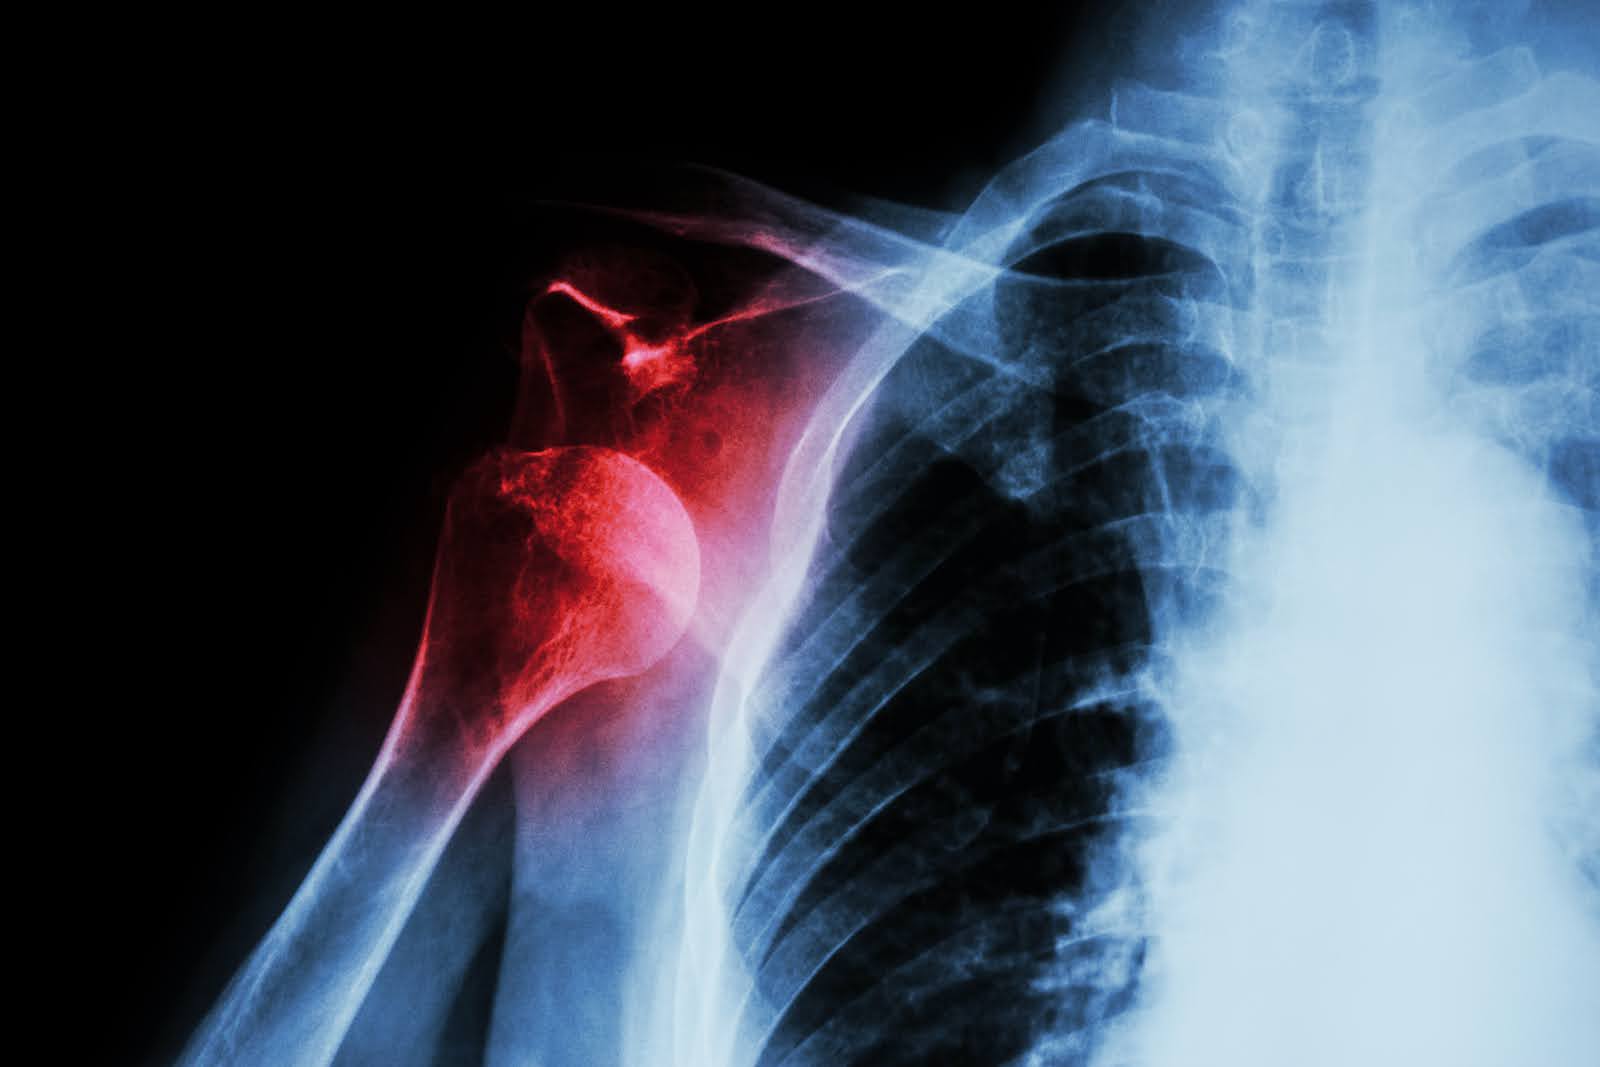

Fractures and dislocations of the shoulder and elbow require urgent, specialist assessment. Mr Baring offers rapid private access for expert diagnosis, surgical fixation, and long-term recovery planning.

Rapid imaging (X-ray + CT where needed). Non-surgical management for stable fractures — sling, physio, close monitoring. Surgical fixation or reconstruction for displaced or complex fractures. Second opinions welcome.